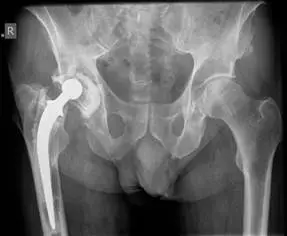

صورة توضيحية لـ تآكل مفصل الورك الصناعي: الأسباب والعلاج في صنعاء | د. محمد هطيف

السيدة فاطمة، 68 عامًا، من ريف صنعاء، كانت تعاني من ألم شديد في الورك الأيمن لسنوات عديدة بعد عملية استبدال مفصل ورك أولية أجريت قبل 15 عامًا. بدأ الألم خفيفًا ثم تزايد ليصبح معيقًا، مما منعها من رعاية أحفادها وأداء مهامها اليومية البسيطة. أظهرت الأشعة السينية علامات واضحة لتآكل بطانة البولي إيثيلين وتحلل العظم حول المكون الحقي.

بعد استشارتها الأستاذ الدكتور محمد هطيف، الذي أجرى تقييمًا شاملاً ودقيقًا، شرح لها الدكتور محمد طبيعة التآكل وضرورة جراحة المراجعة. بطمأنينة وخبرة، خطط الدكتور محمد للجراحة بدقة فائقة، مستخدمًا تقنيات متقدمة لإزالة المكونات المتآكلة وترقيع العظم المتآكل قبل زرع مفصل جديد.